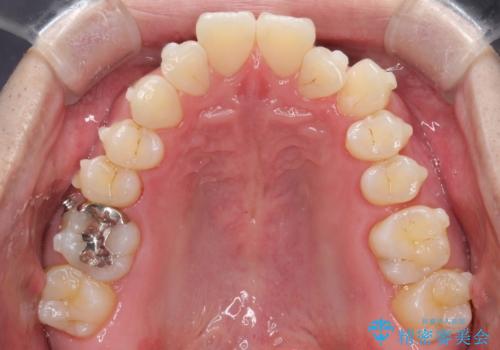

- 前歯の凸凹と顎の偏位を主訴に来院されました。

下顎の偏位を認めましたが、外科矯正を希望されなかったためできる範囲で顎の偏位を治すことができるよう治療を行なっております。

治療開始前に、下顎位の評価をおこなうことで、完成度の高い治療を行うことができました。